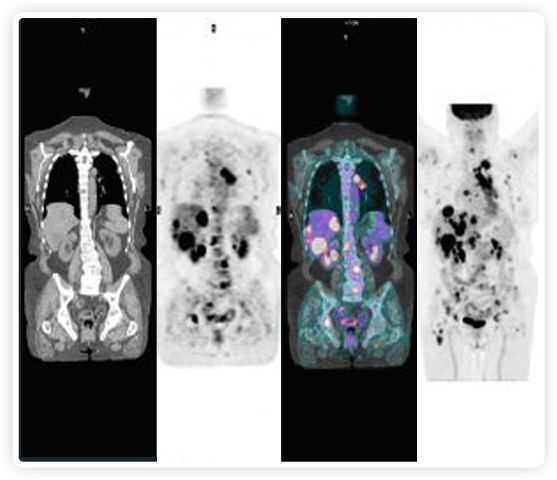

正電子發(fā)射斷層掃描(PET)是癌癥檢測中已建立的成像標準,與其他成像方式相比,PET能提供高靈敏度和特異性的圖像。

到目前為止,放射腫瘤學中(使用的圖像主要是結(jié)構(gòu)性的,而PET圖像可以提供生物學信息。通過使用注射示蹤劑,例如18-FDG,PET可以描繪腫瘤的代謝活性,使其“點亮”。(FDG是用于可視化癌癥代謝的最廣泛使用的示蹤劑。與正常組織相比,腫瘤細胞保留更高水平的FDG。)不同的PET示蹤劑可以識別腫瘤的不同生物學特征,例如特定生物標志物抗原(例如,PSMA)或甚至探測免疫系統(tǒng)本身(例如,PDL1表達或活化的T細胞)。